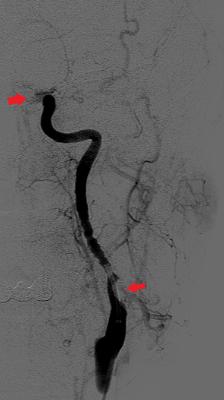

颈动脉造影:血管近端可见充盈缺损(下箭头) , 提示颈动脉夹层 , 远端血管(上箭头)因血栓堵塞而不显影 。

几个小时的奋战后 , 神经外科团队通过微创介入手段将章一颅内血管里的栓子一一取了出来 , 使血管再通 , 同时用颈动脉支架修复了颈动脉夹层 , 避免了后续可能发生的更大悲剧 。

取栓手术后(右图) , 颅内血管被打通后重新显影 , 颈动脉夹层被支架修复 。